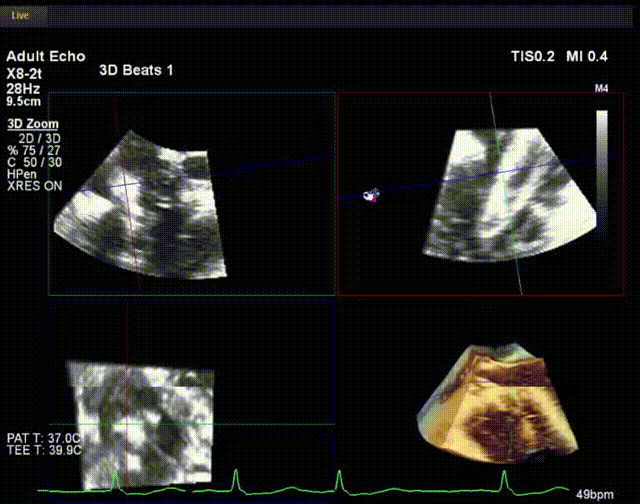

術(shù)中超聲

陸方林教授通過(guò)遠(yuǎn)程線上帶教的方式,與林逸賢教授團(tuán)隊(duì)共同完成了此次LuX-Valve Plus人工瓣膜的首例植入。術(shù)后食道超聲提示三尖瓣反流完全消失,無(wú)瓣周漏,且LuX-Valve Plus人工瓣膜的兩個(gè)夾持鍵成功抓取瓣葉,錨定牢固,人工瓣膜穩(wěn)定性良好。